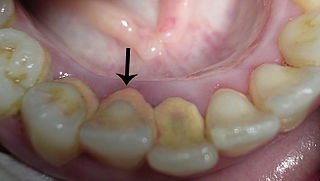

Tandsteen is een verharde laag tandplak die bestaat uit een mineralenlaag. Het speeksel in de mond is rijk aan calcium en fosfaat, dat kan neerslaan op de tanden. Deze zouten reageren met de aanwezige tandplaque en hierdoor ontstaat tandsteen. Een hoge pH-waarde in de mond leidt tot snellere vorming van tandsteen, terwijl gaatjes juist worden veroorzaakt door een lage pH-waarde. Tandsteen is poreuzer dan tandglazuur, waardoor het gemakkelijker verkleurt. Tandsteen boven het tandvlees uit zich meestal als een gele of bruine kleur op de tanden en kiezen. Tandsteen kan ook op of onder de tandvleesrand gaan zitten waardoor het tandvlees geïrriteerd kan raken. Dit veroorzaakt gingivitis. Verharding van tandplaque in tandsteen, kan snel gebeuren, indien de tandplaque niet optimaal verwijderd wordt (zelfs al na 4 dagen na een gebitsreiniging). De meest voorkomende plekken hiervoor zijn bij de uitmondingen van de grote speekselklieren zoals de ondertongse- en de oorspeekselklieren. De tandsteenvorming ontstaat dan aan de binnenkant van de ondertanden en aan de wangzijde van de bovenkiezen.

Gingivitis is een ontsteking (=itis) van de gingiva oftewel het tandvlees. Gingivitis (ontsteking van de gingiva) wordt in de volksmond ontstoken tandvlees genoemd. Ontstoken tandvlees kan men herkennen aan roodachtig (vaak gezwollen) tandvlees dat bij aanraking gemakkelijk gaat bloeden. Gingivitis (tandvleesontsteking) ontstaat door de ophoping van tandplaque en tandsteen rondom tanden en kiezen. Omdat tandvleesontsteking in lang niet alle gevallen goed waarneembaar is, is het belangrijk dat u regelmatig een bezoek brengt aan een mondhygiëniste. Gingivitis kan genezen door een goede mondhygiëne toe te passen. Uiteraard, indien er tandsteen aanwezig is, dient dit professioneel te worden verwijderd. Als de ontsteking meer weefsel dan alleen het tandvlees omvat, dan spreken we van parodontitis.